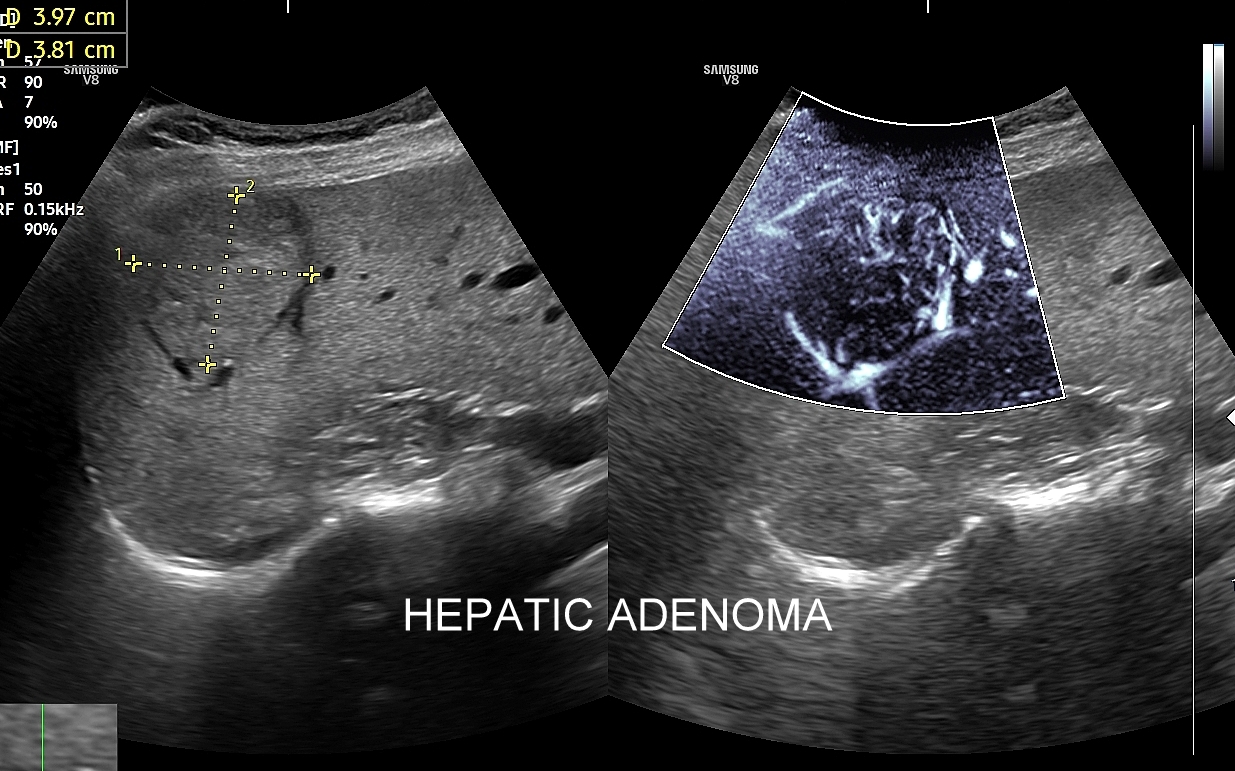

Badanie USG z kontrastem najczęściej wykorzystuje się do oceny zmian ogniskowych w wątrobie, potocznie nazywanych guzami wątroby, z których wiele ma na tyle specyficzny obraz mikrounaczynienia w obrazowaniu CEUS, że możliwe jest uniknięcie konieczności badania obciążającymi metodami TK lub MRI. Badanie CEUS w przeważającej większości pozwala odpowiedzieć, czy zmiana ogniskowa wątroby ma cechy złośliwe czy łagodne. Dodatkowo CEUS jest pomocny do wykrywania przerzutów do wątroby pochodzących z nowotworów w innej lokalizacji. W przypadku przerzutów o wielkości mniejszej niż 1 cm CEUS ma większą czułość aniżeli badanie TK.

CEUS jest badaniem w czasie rzeczywistym pozostającym pod kontrolą operatora, podczas którego możliwe jest wykonanie próby czynnościowej oraz natychmiastowe powtórzenie całego badania w razie konieczności. Możliwości takich nie dają ani TK ani MRI. Dodatkowo CEUS cechuje się o wiele większą rozdzielczością czasową w porównaniu do wspomnianych metod, co umożliwia uwidocznienie wczesnej fazy tętniczej unaczynienia podejrzanej onkologicznie zmiany ogniskowej w wątrobie i jej lepszą charakterystykę.

Narządem, w którego diagnostyce najczęściej wykorzystuje się CEUS, jest wątroba; w dalszej kolejności nerki, trzustka, protezy naczyniowe aorty, drogi żółciowe oraz inne narządy wewnętrzne.